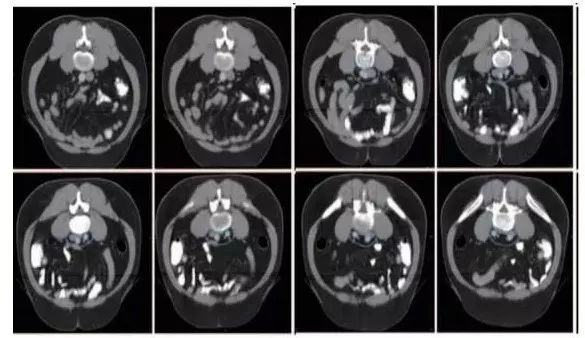

高危淋巴结引流区及高危复发区边界定义及图谱(CT层厚0.5cm,俯卧位)

勾画图谱